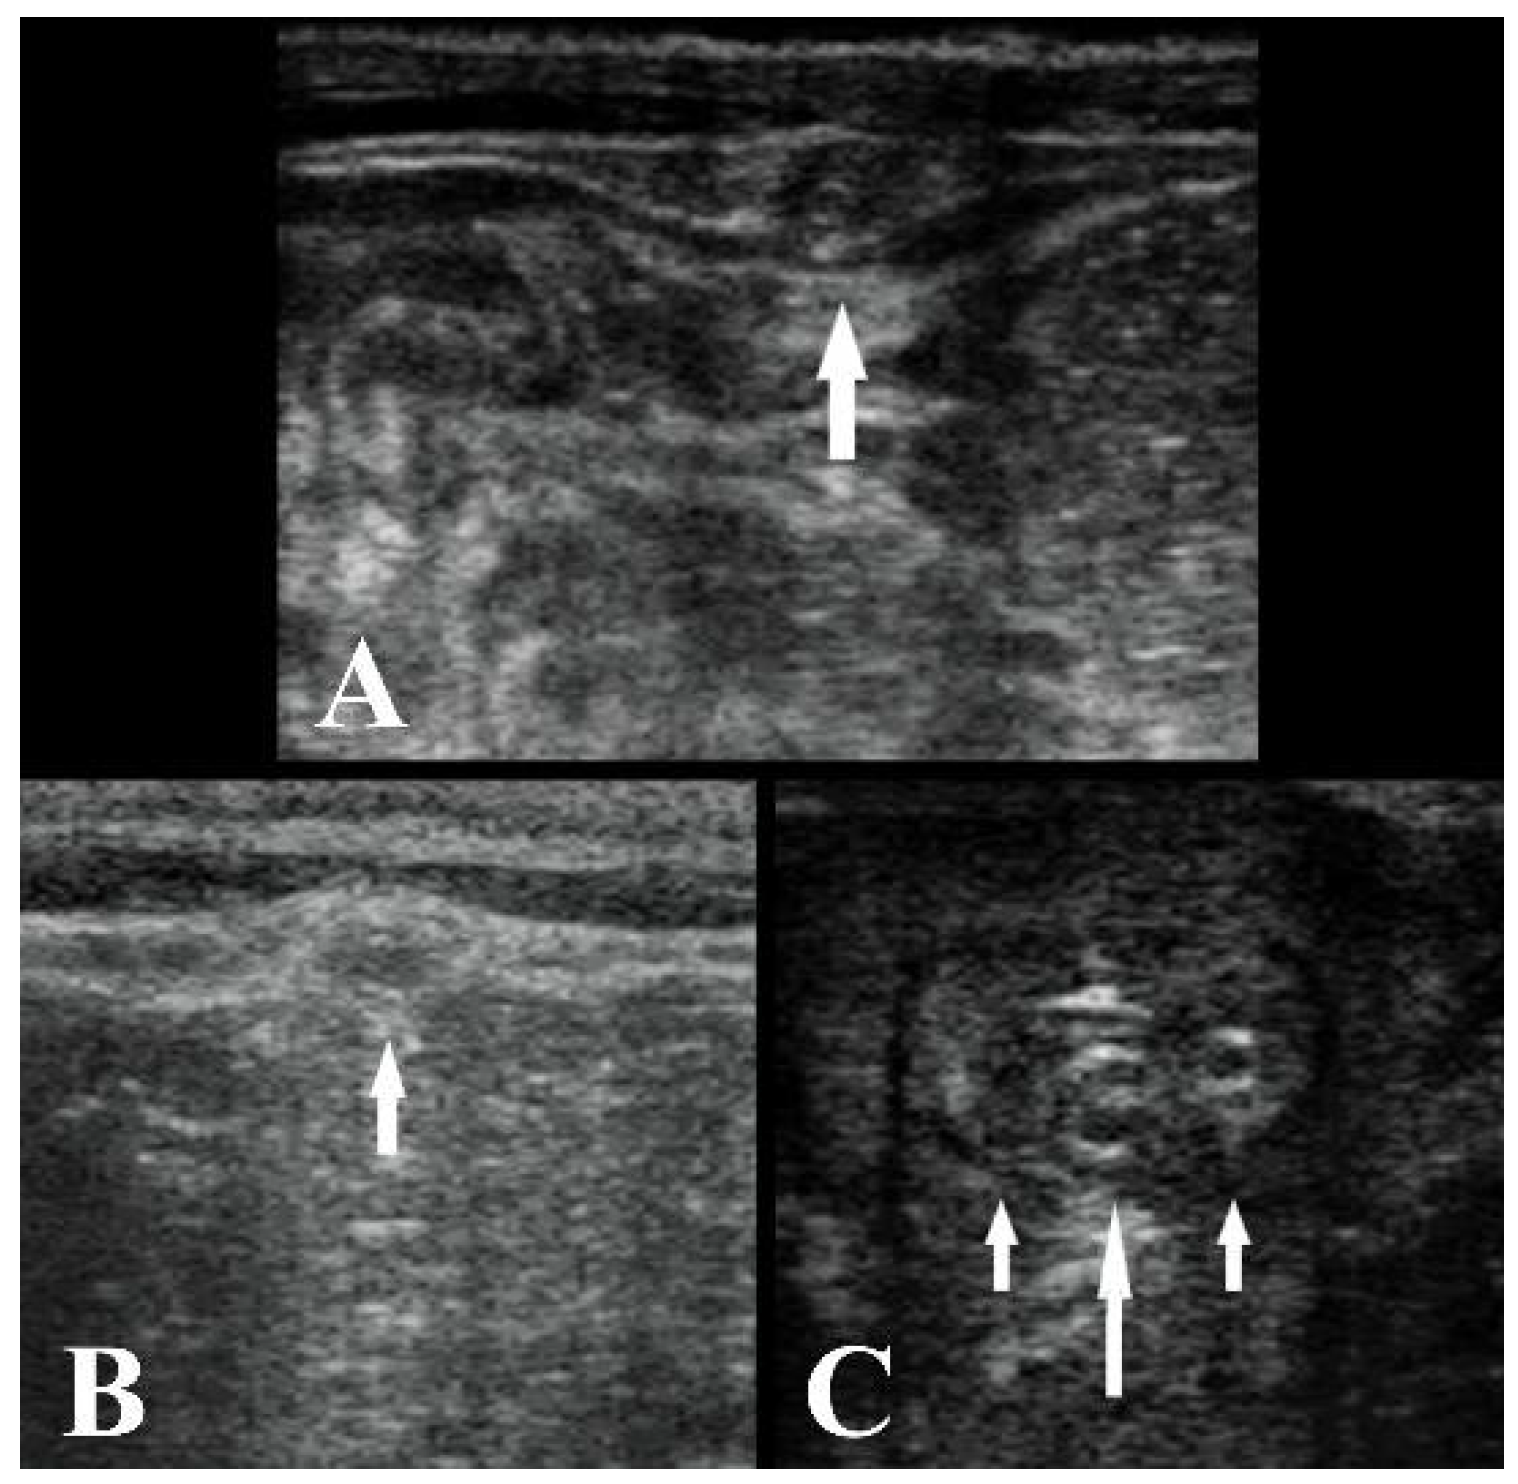

2.2. Ultrasonography Technique

3. Results